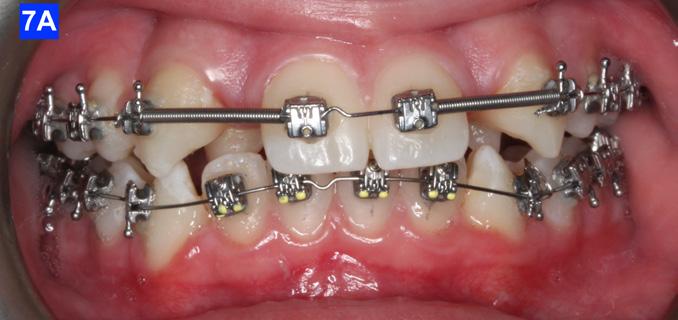

maxillary first bicuspids was the most advantageous way forward. While the parents were contemplating this recommendation, a closed coil spring was added from the maxillary central incisors to the cuspids and attention was directed towards the lower arch. Treatment of the mandible was begun with leveling arch wires (a .014 NiTi followed by a .018 NiTi). In the author’s experience it is often beneficial to delay treatment in the arch that requires less correction if the opposing is significantly more complex. (Figure 7-A).

When the maxillary teeth were leveled, we placed a .018 SS arch wire and an OCS to create as much space as possible for the lateral incisors. This technique also allowed us to increase the inclination (torque) of the central incisors as they were too retrusive at the start of the treatment (U1/SN 91°). The maxillary lateral incisors were now completely retracted (Figure 6-A, B).

After 18 months of treatment, there was no more space to further distalize the cuspids as they were already touching the first bicuspids. This left inadequate room for the lateral incisors. The posterior sextants could not be distalized as there was only 1.5 mm overbite, and the pt. was severely hyper-divergent (NS/GoM - 40° vs. Norm of 32° +-3). Therefore, the author felt that extraction of the

Finally, after 21 months of treatment, the patient and the parents consented to the odontectomy of the maxillary first bicuspids. The informed consent forms for the extractions and placement of TADs were signed by the parent, and all questions were answered. Risks, benefits, alternatives, and the result of no treatment at all were reviewed. Immediately after the odontectomy of #14(5) and #24(12), 1.6 x 8.0 mm AnchorPro (OrthoOrganizers) TADs were placed just mesially to the maxillary second bicuspids.6 In office power arms (a .018 x.025 SS) were fabricated and bonded to the buccal surface of the maxillary cuspids, just above the bracket.7 The purpose of the power arm is to place the applied force as close to the center of resistance of the tooth as possible. In this manner the line of action (power hook to the TAD) is parallel to the occlusal plane. The source of the force is an EC, and it must be replaced at least bi-weekly. Both arches had a .018 SS arch wire. There was a small off-center bend (tip-back, gable bend) “V” pointing occlusally, mesial to the maxillary second bicuspids.8 The purpose of this bend is to keep the roots parallel during the translation of the cuspids. There was a small OCS between #21(9) and #23(11) to shift the maxillary midline to the right. Another OCS was placed between #32(23) and #34(21) to facilitate the alignment of the mandibular left cuspid (Figure 8-A, B, C, D).

Figure 5A: Adrian “U” bend spring, frontal view Figure 5B: Adrian “U” bend spring, right lateral view Figure 5C: Adrian “U” bend spring, left lateral view Figure 5D: Continuation of retraction, occlusal view Figure 6A: OCS between the central incisors an the cuspids Figure 6B: Retraction of the lateral incisors is completed Figure 7A: Starting treatment on the mandibular arch, frontal view